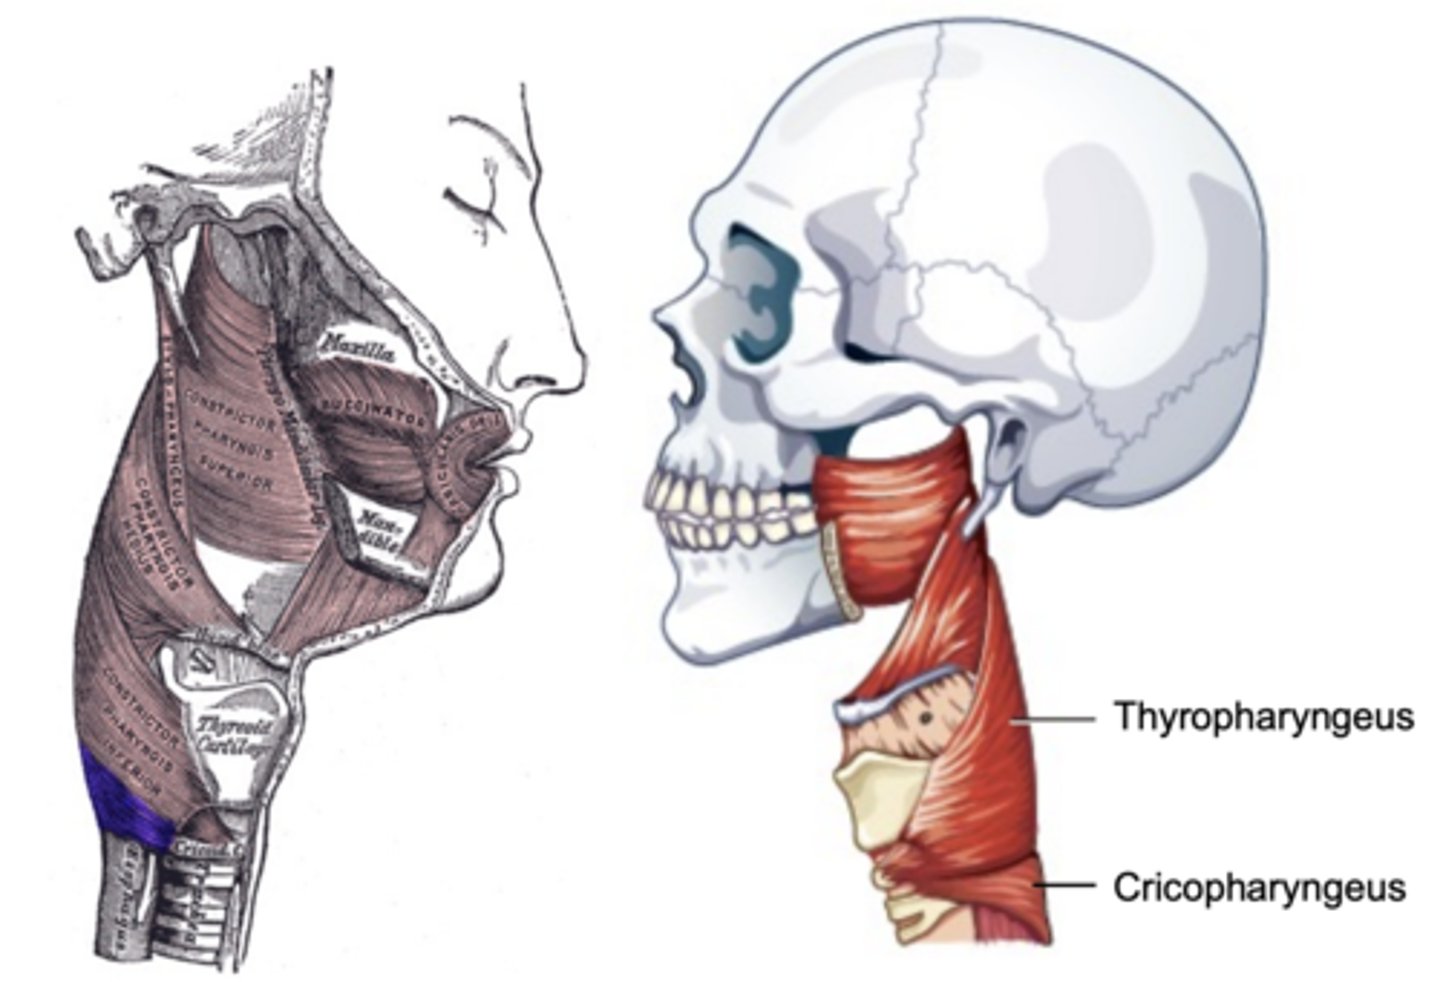

Inferior Constrictor -

Thyropharyngeus Description

Inferior Constrictor consists of the

Thyropharyngeus and the Cricopharyngeus

Inferior Constrictor is thickest and strongest of constrictor muscles

Thyropharyngeus is the majority of the Inferior Constrictor

Origin -thyroid cartilage

Course - fans out posteriorly and medially

Insertion - midline raphe

Action - reduce diameter pharynx

Inferior Constrictor -

Thyropharyngeus Figure

Inferior Constrictor -

Cricopharyngeus Description

Part of Inferior constrictor

Muscular component of upper esophageal

sphincter (UES)

Origin - cricoid cartilage

Course - fans out posteriorly and medially

Insertion - midline raphe

Action - open and close upper esophageal

sphincter

Inferior Constrictor -

Cricopharyngeus Figure